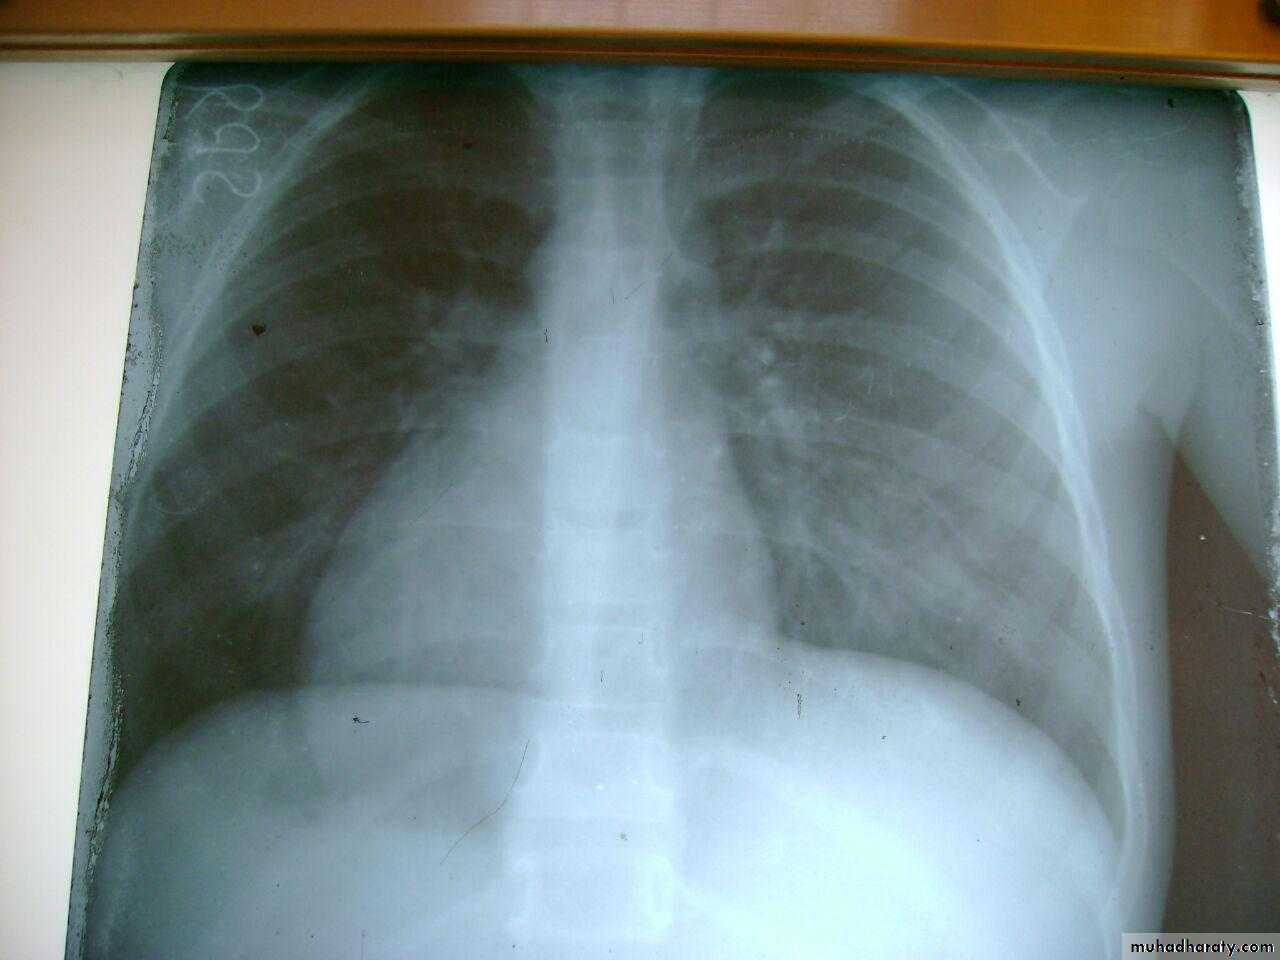

3 month infant presented with cough & dyspnea

Xray shows hyperinflated chest (depresed diaphragm , > 6 ribsMay be bronchiolitis

Hyperinflated chest